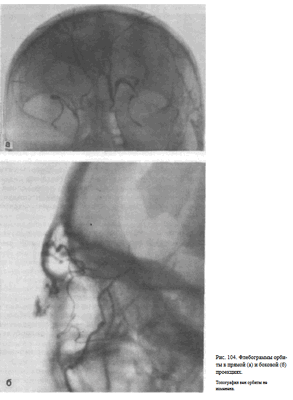

Информативность исследования. Топография верхней глазничной вены постоянна. В норме на флебограмме орбиты в боковой проекции верхняя глазничная вена выявляется под верхней ее стенкой. Она имеет плавные изгибы. Часто видны коллатеральные вены, соединяющие ее с нижней глазничной веной, менее постоянной в своей топографии. На флебограмме

орбиты в прямой задней проекции верхняя глазничная вена отображается в форме ромба (рис. 104, а, 6). Отклонение в пробеге верхней глазничной вены, оттеснение ее, а также обрыв, как правило, связаны с объемным процессом в полости глазницы.